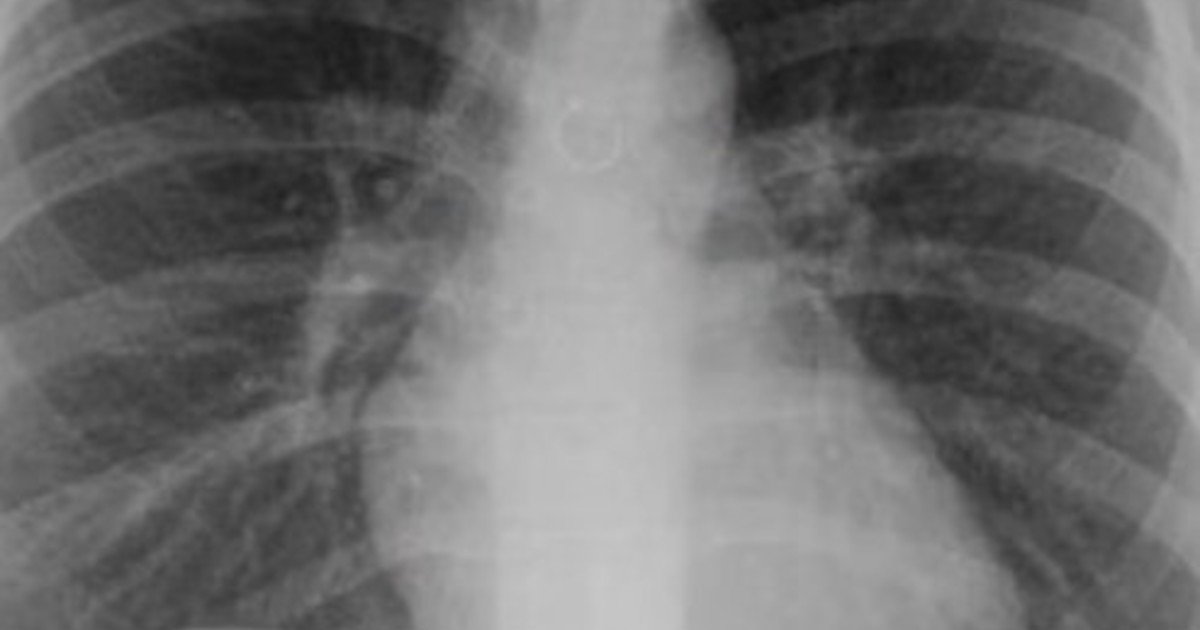

Empezó a toser y un mes después descubrió que tenía un piercing nasal en uno de sus pulmones: «Los médicos estaban impactados»

• Una joven reveló una impactante experiencia personal vinculada a un problema de salud.